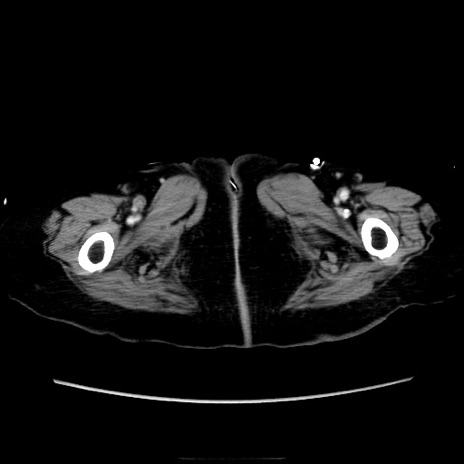

症例40(横断像)

【症例】90歳代女性

【主訴】腹痛・嘔吐

【現病歴】 食欲低下、嘔吐があり昨日他院受診。肺炎と診断され入院となる。入院後より腹部全体に圧痛あり。胃管留置され経過みていたが、症状持続するため、

当院転院となる。

【既往歴】胸椎圧迫骨折、胆石症

【身体所見】腹部:中央に激痛あり、圧痛あり、反跳痛不明

【データ】WBC 17100、CRP 18.82

横断像